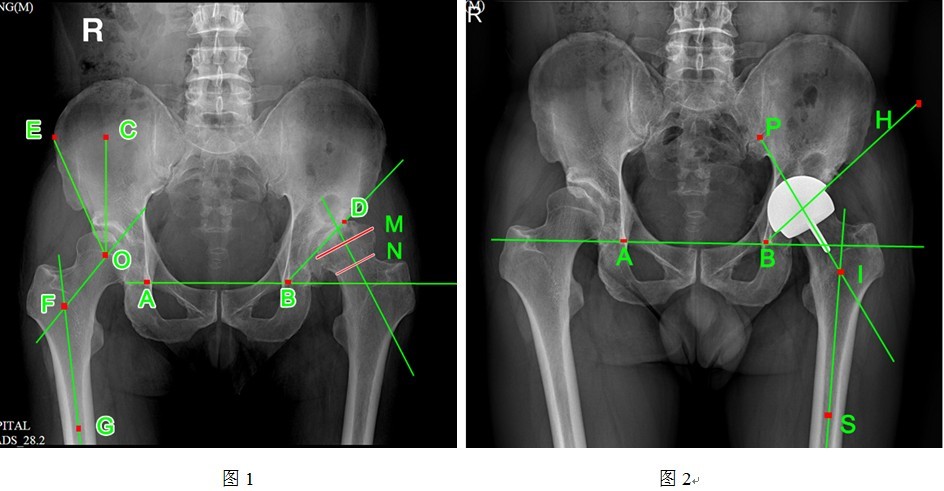

术前、术后均拍摄标准骨盆正位片,单侧髋关节正侧位片,摄片时双足内旋15度。通过南方医科大学研发的PACS系统测量术前髋臼Sharp角与术后髋臼外展角、术前头颈比例、术前颈干角与术后柄干角、术前CE角以及术后髋臼杯假体外露情况(具体测量方法详见图1~2)。按照髋臼3区和股骨柄正位7区、侧位7区描述透亮带。

①髋臼角:AB与BD的夹角(A 、B为双侧泪滴投影点,D为髋臼外上缘投影点);

②CE角:CO和OE的夹角(O为股骨头中心点,CO为经过O点的垂线,OE为自股骨头中线点至髋臼外上缘的连线);

③颈干角:GF与OF的夹角(GF为股骨轴线,OF为股骨颈轴线);

④头颈比:M/N的数值(M线为股骨头直径,N线为股骨颈直径);

⑤髋臼外展角:AB和BH的夹角(AB为双侧泪滴连线,BH为髋臼边缘投影);

⑥柄干角:PI与SI的夹角(PI为股骨头中心杆轴线,SI为股骨轴线)。